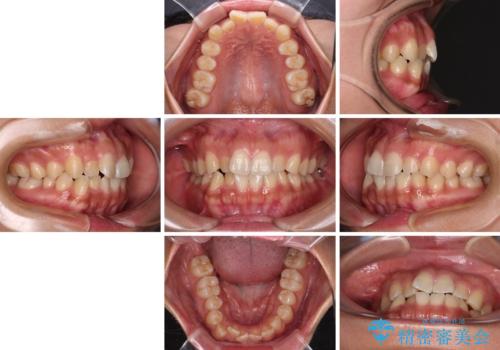

デコボコと捻れて前に飛び出した歯列 抜歯矯正でスッキリした口元に

- 前歯のデコボコと口元の突出感を気にして来院された患者様です。

非抜歯矯正ではデコボコを解消することでより口元が突出してしまうため、上下左右の小臼歯4本の抜歯を行い、ワイヤー装置による矯正治療を行うこととしました。

上顎小臼歯の歯根が左右ともに大きく曲がっており、スペースクローズに時間がかかってしまいました。